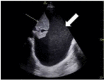

Case report: A 78-year-old year old male who presented with stroke symptoms and after tPA administration developed a retropharyngeal hematoma requiring intubation and surgical intervention.